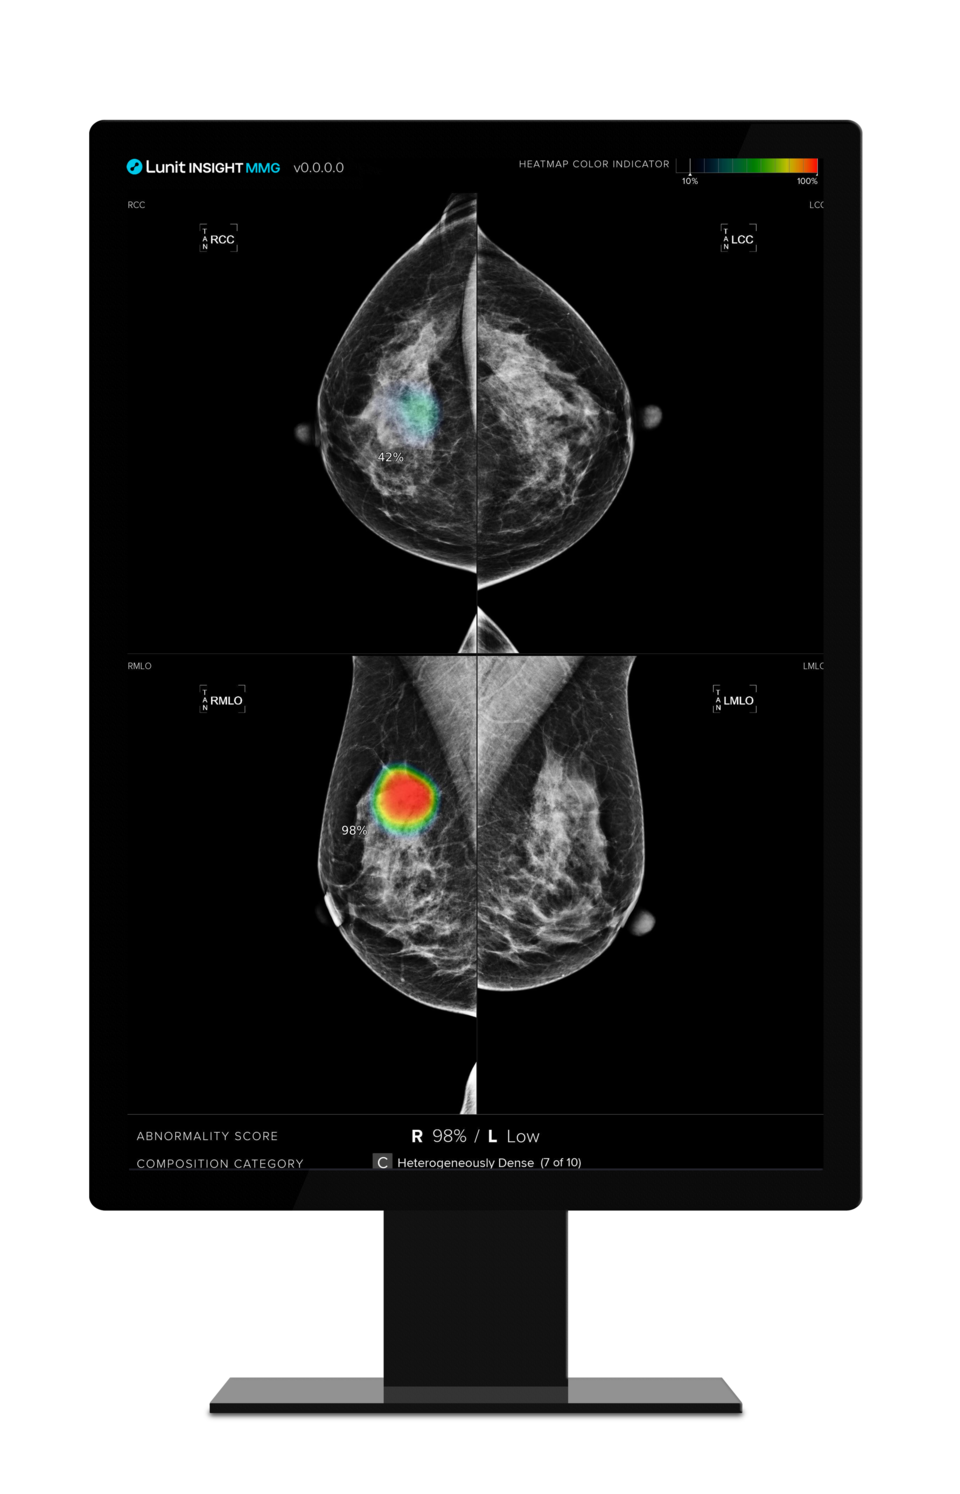

Lunit, a forefront provider of AI-based solutions for cancer diagnostics and therapeutics, has announced the validation of its AI-powered mammography analysis solution, Lunit INSIGHT MMG, for standalone breast cancer detection. This confirmation comes from a study recently published in European Radiology, led by Dr. Johanne Kühl and Dr. Mohammad Talal Elhakim at the University of Southern Denmark. The study compared the performance of Lunit's AI system to first-reading breast radiologists across a comprehensive screening population.

Key findings revealed that when Lunit INSIGHT MMG's cut-off score matched the first reader mean specificity, its overall accuracy was statistically equivalent to that of radiologists. However, aligning the AI threshold with the first reader mean sensitivity showed slightly lower specificity (97.5% vs. 97.7%), positive predictive value (17.5% vs. 18.7%), and a slightly higher recall rate (3.0% vs. 2.8%) compared to first readers.

The study indicates the potential for Lunit INSIGHT MMG to replace first readers in a mammography double-reading setting by utilizing an appropriate cut-off score. Cancers detected by AI but missed by radiologists suggest that integrating AI support in screening could increase overall detected cancer rates without significantly altering the clinicopathological characteristics of the detected cancers.